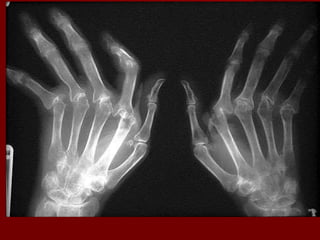

X-rayX-ray

– of all the lab tests, x-ray changes are most specific forof all the lab tests, x-ray changes are most specific for

rheumatoid arthritis. However, they are not sensitiverheumatoid arthritis. However, they are not sensitive

and usually are negative during the first 6 months ofand usually are negative during the first 6 months of

the diseasethe disease

– the earliest changes occur in the wrist or feet andthe earliest changes occur in the wrist or feet and

consist of soft tissue swelling and juxta-articularconsist of soft tissue swelling and juxta-articular

demineralization.demineralization.

– Later, diagnostic changes consisting of joint spaceLater, diagnostic changes consisting of joint space

narrowing and erosions develop.narrowing and erosions develop.

– Diagnostic changes also occur in the cervical spineDiagnostic changes also occur in the cervical spine

with C1-C2 subluxation, but this can take severalwith C1-C2 subluxation, but this can take several

years to develop.years to develop.